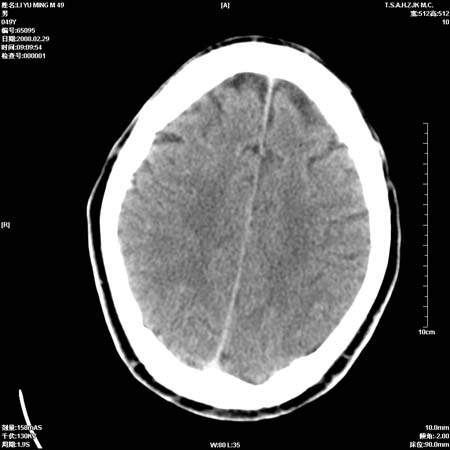

男性, 49岁, 头痛, 行ct检查后, 我科一名大夫报了蛛网膜下腔出血, 请大家讨论!

大脑纵裂池及鞍上池应该有蛛血

可能为正常。间隔一周蛛血应基本吸收;再过一周复还是这样应该可以肯定了。

一周时间密度未见改变,考虑为正常图像(脑动脉硬化?)。